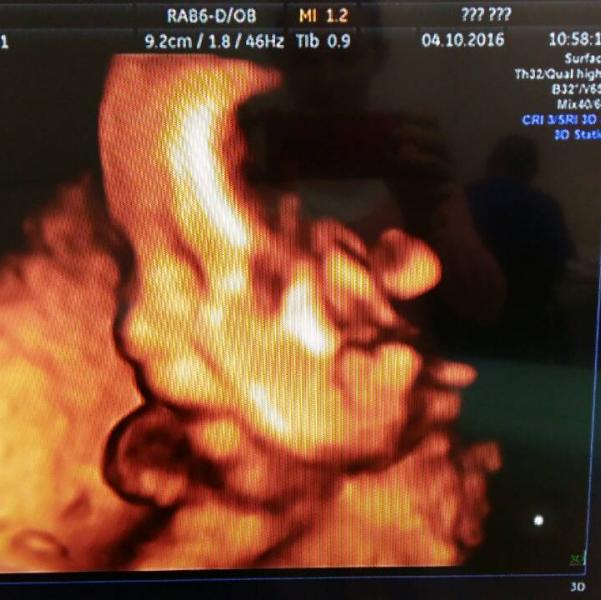

Сыночка наш славненький мы тебя любим и очень очень ждем с нетерпением!!!!

@kermama, открытое овальное окно в сердце у ребенка, низкая плацентация все о чем напугали все в норме